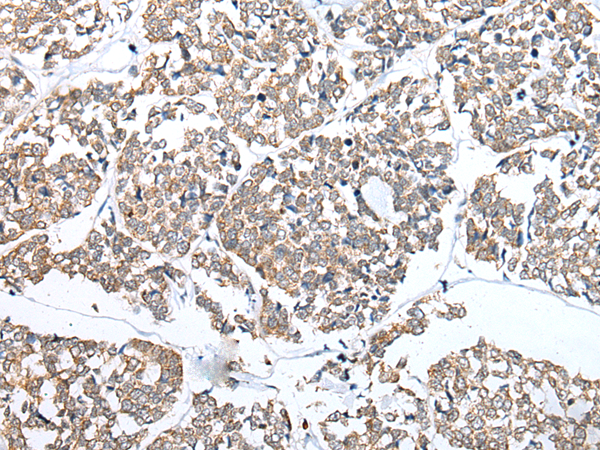

分类: 科研抗体货号: P09096别名:应用: IHC反应种属: Human